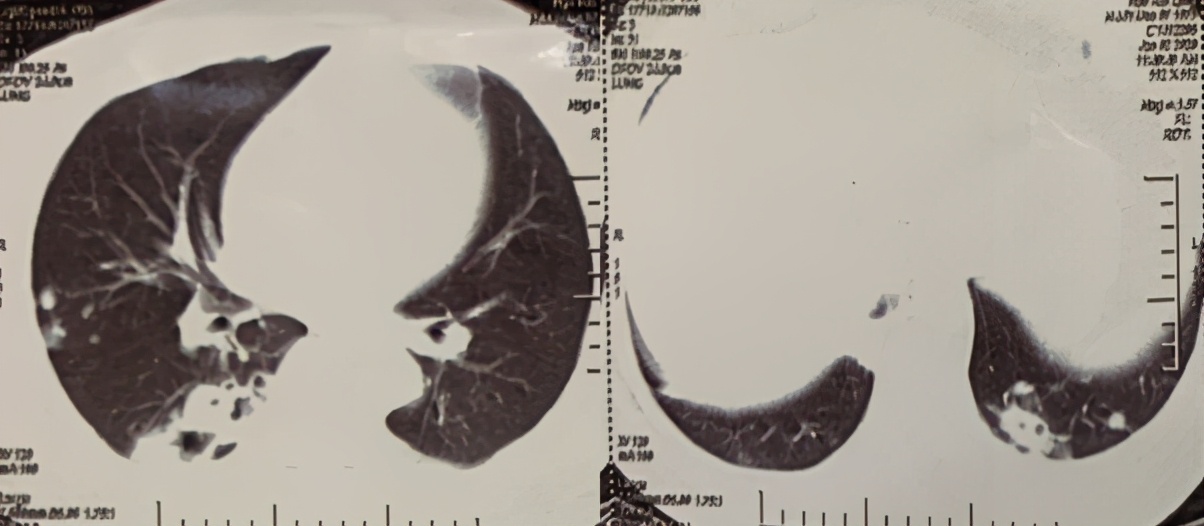

感染病科潘珏教授是位干练又细心的女医生。看到老何走进诊室气都喘不匀,赶紧让他坐下;十几张CT片一一看过。

“病人这个年纪,确实要警惕肿瘤”;

“病灶基本没吸收,不太像普通细菌感染”;

至此,医生说老何的疾病明确诊断了,叫做新生隐球菌肺炎。医生说隐球菌是一种真菌,新生隐球菌是国内最常见的隐球菌,主要存在于土壤,腐烂的木材,和鸟类排泄物尤其是鸽粪中,最常引起的是肺部和脑子的感染。老何生病应该就是长期接触腐烂木材,吸入了大量隐球菌孢子、进而感染了肺部;一般说来,隐球菌肺炎的症状大多不明显,以乏力、盗汗和干咳为主,老何这个咯血症状是隐球菌肺炎里比较少见的。给他安排的头颅磁共振和腰穿脑脊液检查,是为了排除脑子感染,万幸的是,老何脑子里没有病灶。

“老何胸部CT上病灶有吸收,我们批准你回家啦。回去吃药,病灶会继续好转的。“潘教授也向老何一家报喜